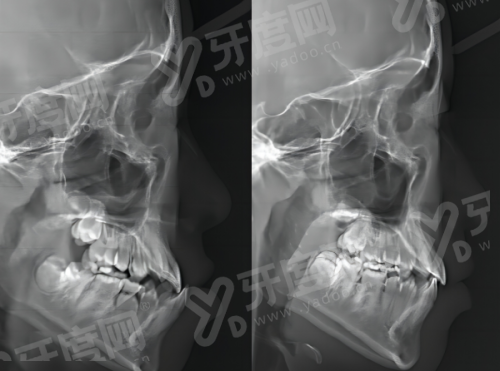

① 口腔科设有门诊部和口腔颌面外科病区,门诊部设有多个专精亚科和标准化器械灭菌中 心,拥有精良的全电脑牙科综合治疗椅、口腔数字化曲面断层全景X光机等设备,为患者提供了良好的治疗条件。

② 开展牙体牙髓病、牙周病、儿童口腔、口腔颌面外科、口腔修复、口腔正畸、口腔颌面医学影像科等新技术项目 30 余项,业务范围广泛,能满足不同患者的口腔需求。